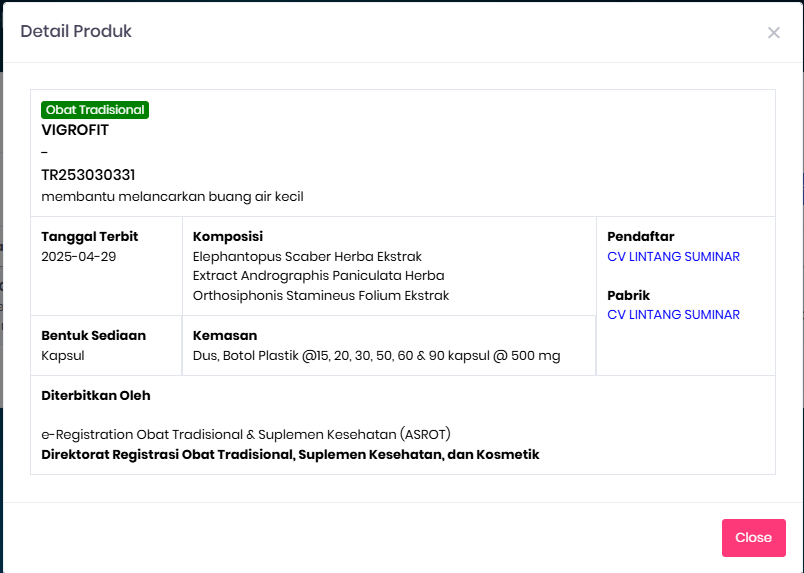

VIGROFIT Terbukti Tersertifikasi BPOM

Obat kencing nanah rekomendasi dokter sudah resmi BPOM & MUI

BPOM – TR253030331

Sertifikasi Aman & Legal

Produk bersertifikat BPOM dan HALAL – aman, terpercaya, dan teruji.